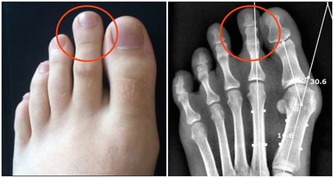

2、下肢動脈閉塞患者

下肢動脈閉塞的表現雖然是下肢缺血,但是熱水泡腳並不能擴張閉塞的血管。當然,通暢動脈的擴張,只是增加了正常組織的血流,而缺血組織可能因為“盜血”現象,更加缺血。相關數據說明,周圍溫度的升高,能夠添加安排的耗氧量,加重缺血。